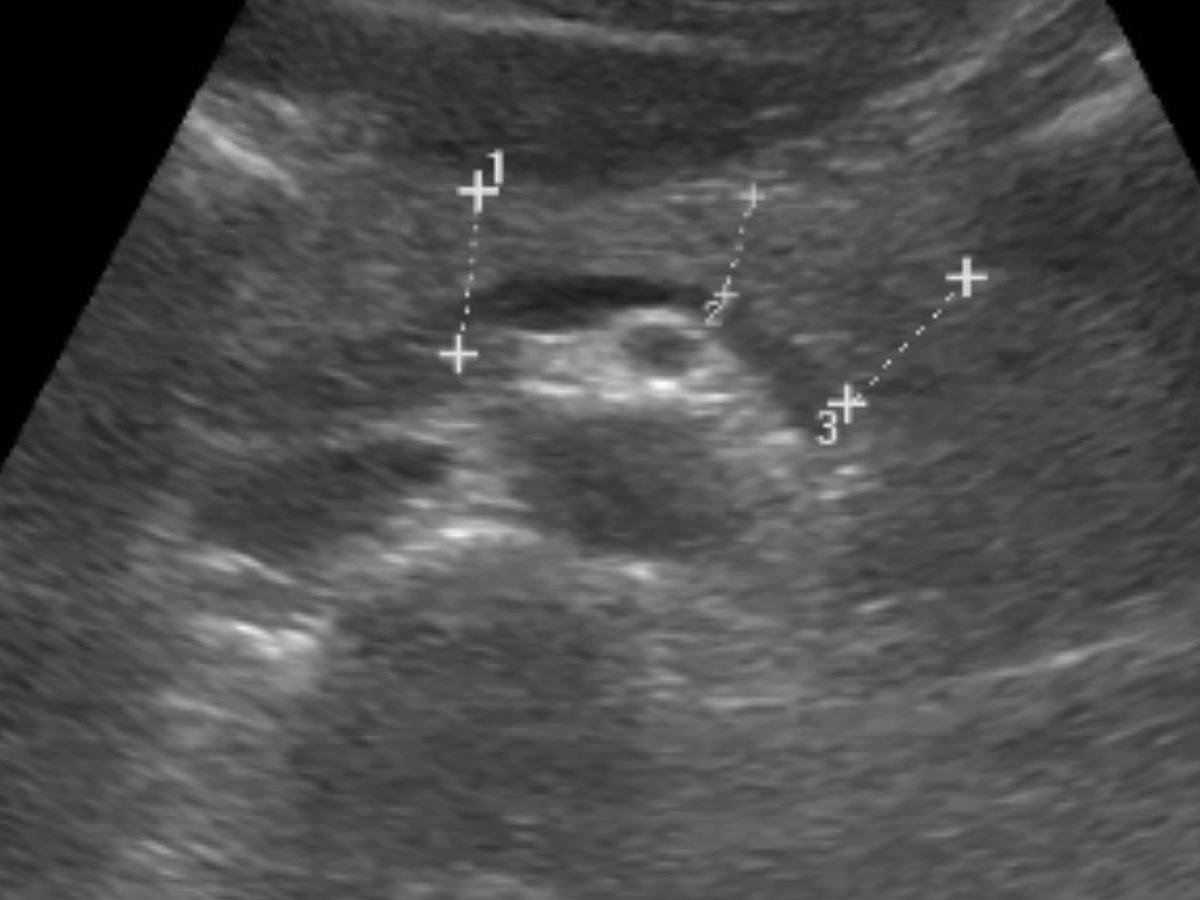

What has been growing, however, is a gallstone in my gallbladder. The gall of it. Literally. It turns out the mysterious abdominal pain I’ve been having on and off for the past six months was not just my digestive system staging a protest. After some tests, the culprit has been identified: a 4 cm gallstone. Apparently my gallbladder decided to start collecting rocks.